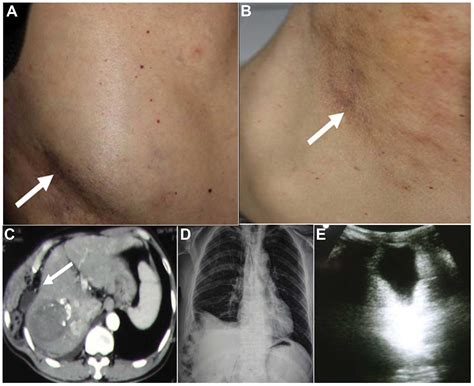

Incisional Hernia: Pathogenesis and Clinical Findings | Calgary Guide

Incisional Hernia: Pathogenesis and Clinical Findings | Calgary Guide